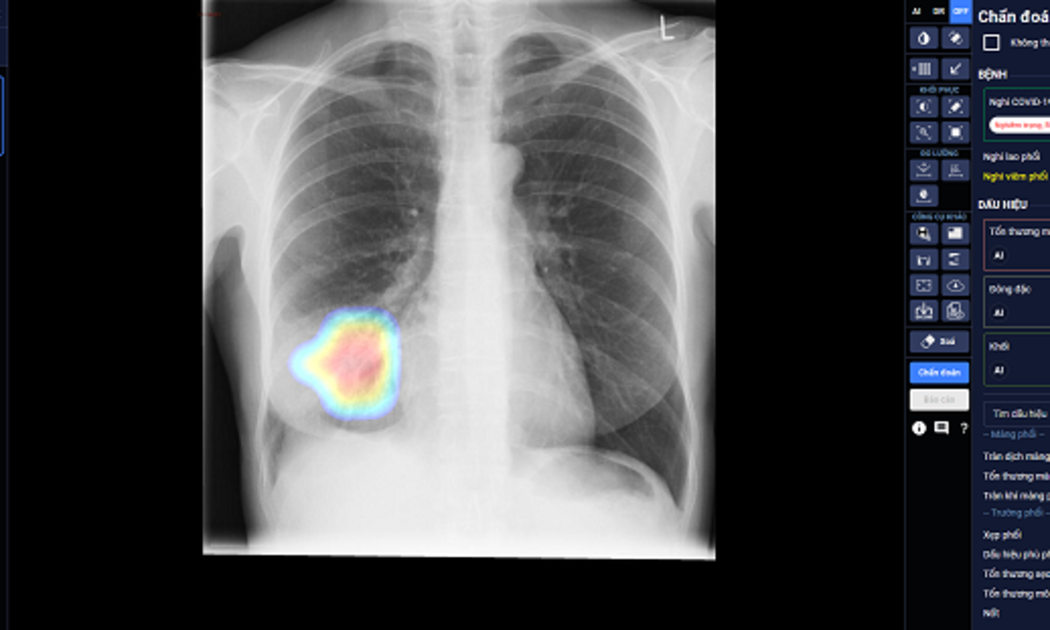

DrAid cho COVID-19 - sản phẩm ứng dụng Trí tuệ nhân tạo (AI) của Công ty Cổ phần VinBrain (thuộc Tập đoàn Vingroup) – vừa được Hội đồng Khoa học Bộ Y tế nghiệm thu và đặc biệt kiến nghị nên sớm đưa vào sử dụng hàng ngày tại các bệnh viện trong giai đoạn COVID-19 đang tiếp tục lây lan như hiện nay. Đây được coi là một công cụ hỗ trợ sàng lọc và tiên lượng điều trị COVID-19 mới hữu hiệu, góp phần chủ động dự phòng và kiểm soát dịch hiệu quả.